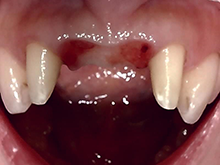

A G C

ガルバノテクニックを用いて作製されるセラミックであり、純金を用いる事によって生体親和性に優れ、歯肉にもやさしく、最適な適合精度と最適なマージン適合性が得られます。

症 例